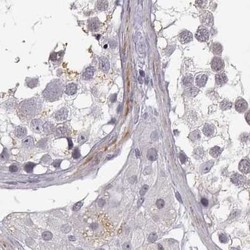

- Immunohistochemistry-Paraffin: VGF Antibody [NBP2-31596] - Staining of human testis.